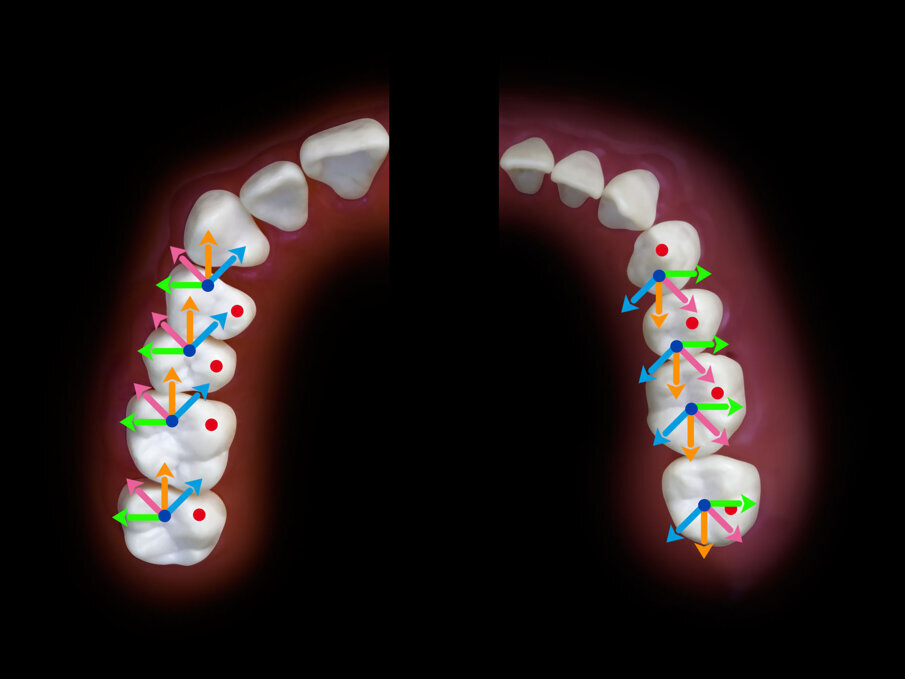

Fig. 1_Protesi a carico immediato con contatti bilaterali simultanei e puntiformi su tutti i denti.

Fig. 3_Direzione dei tragitti di protrusiva dalla massima interscupidazione su edentulia totale. In protrusiva si avranno tragitti lineari a carico degli incisivi.

Fig. 4_Direzione dei tragitti delle cuspidi di centrica a partire dalla massima intercuspidazione.